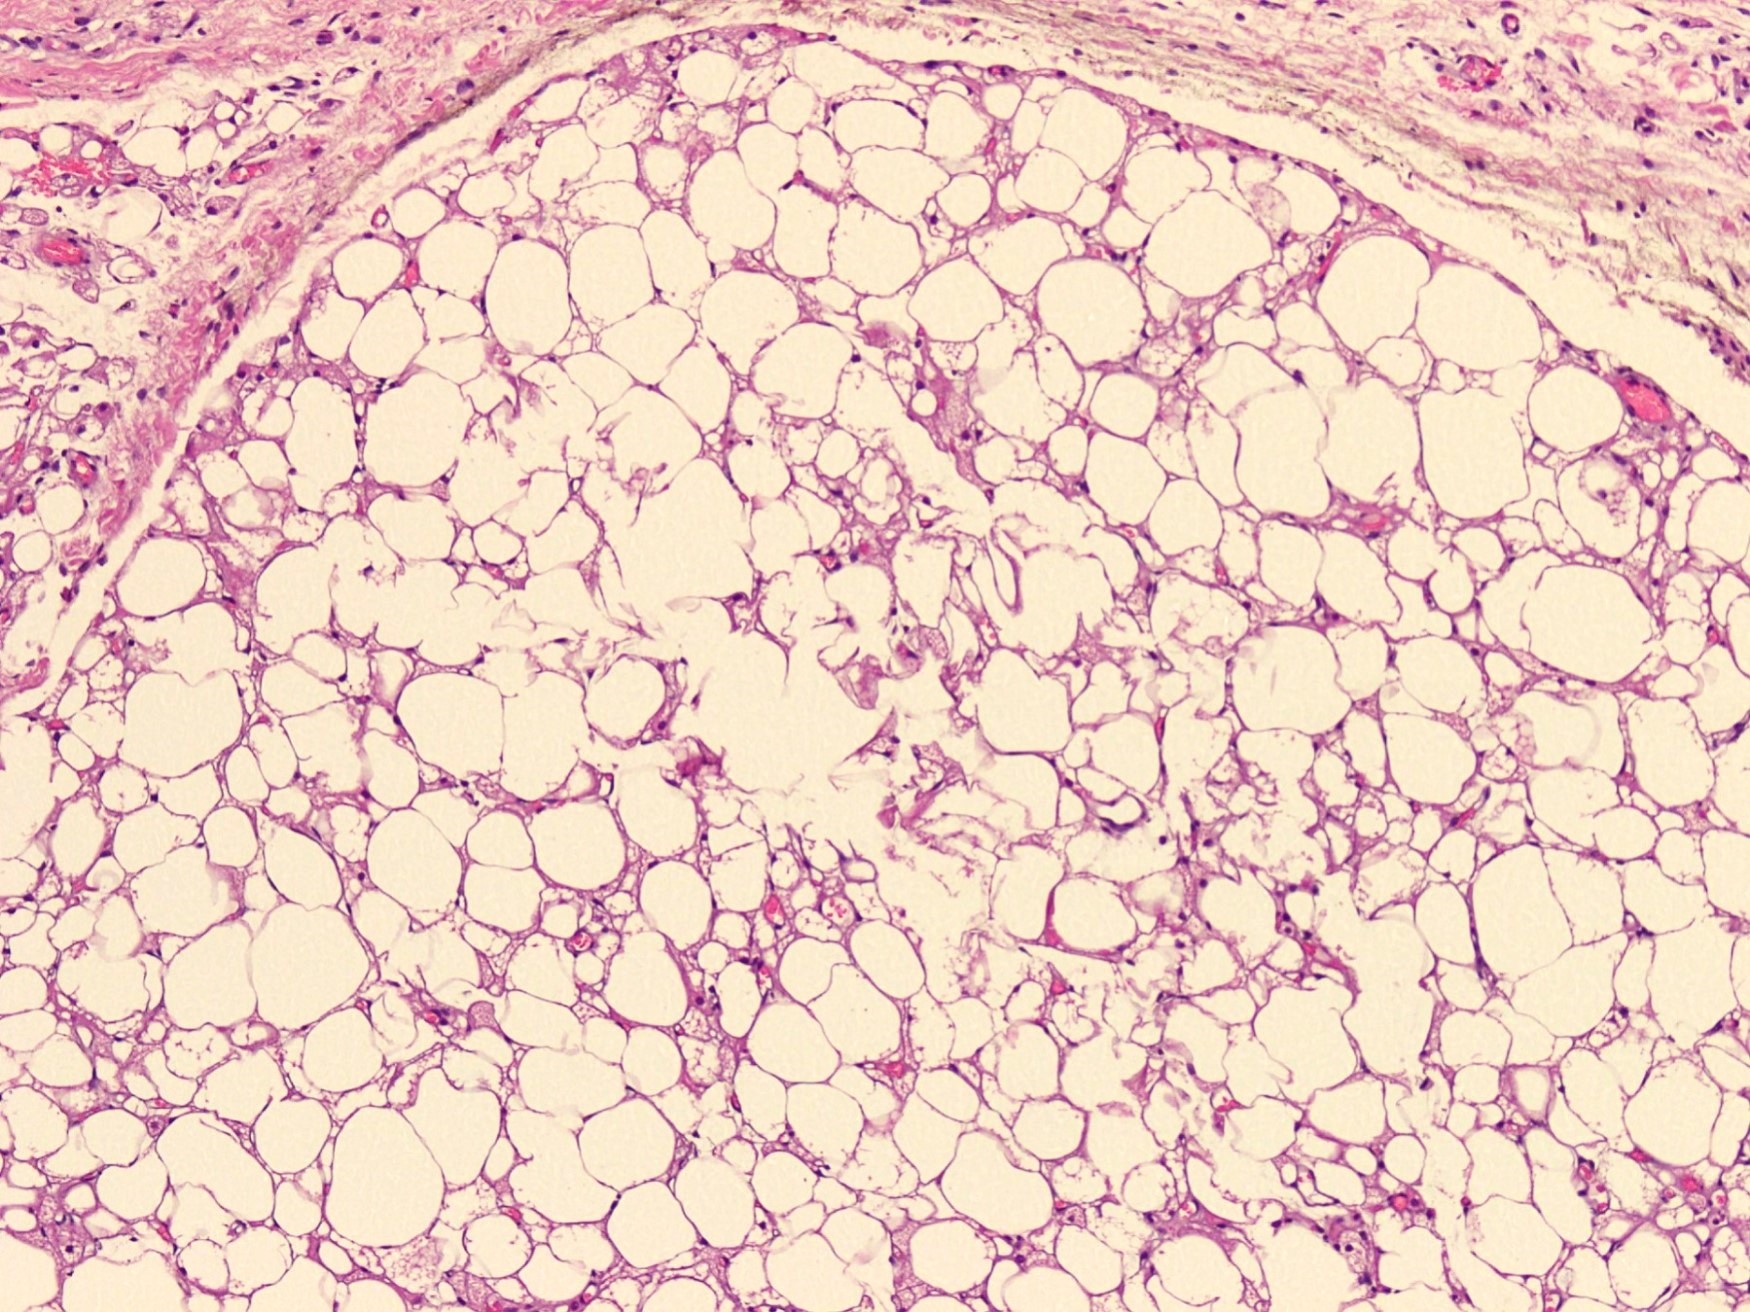

Microscopic (histologic) description

- Neoplastic lesion composed of polygonal brown fat cells with stromal cells in the background (Case Rep Oncol 2017;10:438)

- Large number of pale and eosinophilic brown fat cells with multivacuolated, eosinophilic granular cytoplasm and small central nucleus (about 70%) admixed with variable amount of univacuolated white cells (Case Rep Oncol 2017;10:438, Am J Case Rep 2020;21:e921447, J Comput Assist Tomogr 2019;43:793, J Pathol Transl Med 2017;51:499, Am J Surg Pathol 2018;42:951, Virchows Arch 2021;478:527)

- Multivacuolations resemble lipoblasts

- Morphological variations or subtypes: typical, myxoid (9%), lipoma-like (7%), spindle cell (2%), thick bundles of collagen fibers, presence of mast cells and exclusively containing brown fat cells (Case Rep Oncol 2017;10:438, Am J Case Rep 2020;21:e921447, Virchows Arch 2021;478:527)

- Cytological atypia, necrosis and mitosis is unusual (J Pathol Transl Med 2017;51:499, Am J Surg Pathol 2018;42:951, BMC Surg 2021;21:30)

Microscopic (histologic) images